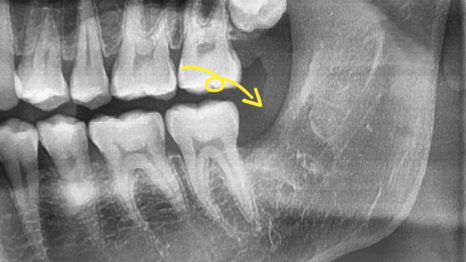

어떤 문제가 생긴 건지 파노라마 사진을 통해

현재 상황을 살펴봤더니

왼쪽 아래쪽에 위치한 부분 매복 형태의

어려운 사랑니가 눈에 띄네요.

이분의 경우 뿌리가 뼈를 움켜지고 있는

얄미운 형태를 갖고 있었던 분이었는데요.